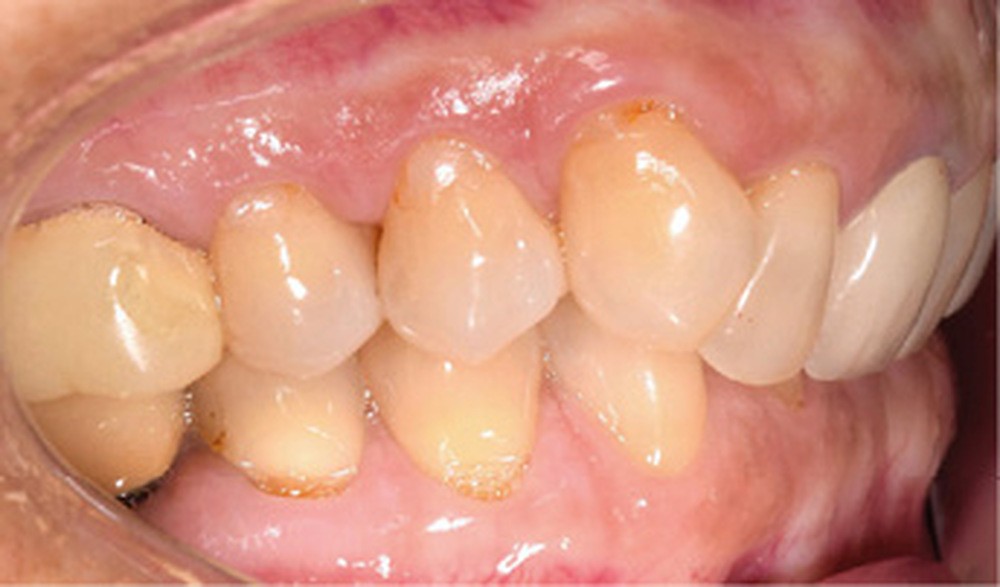

Examen endobuccal (fig. 2a-e)

L’arcade maxillaire est asymétrique et parabolique. Elle présente une mésio-position du secteur 1. On note des rotations mésio-vestibulaire de 13 et disto-vestibulaire de 23 et une palato-version incisive. Les restaurations prothétiques sur 11, 16 et 24 semblent à refaire. L’arcade mandibulaire est asymétrique et parabolique avec une couronne sur implant en 36.

Dans la dimension transversale, on constate une endoalvéolie maxillaire. Dans la dimension sagittale, on observe une classe II plus importante à droite où elle est complète de 5 mm. Le surplomb est absent et la supraclusion totale (6 mm) par supra-alvéolie mandibulaire.